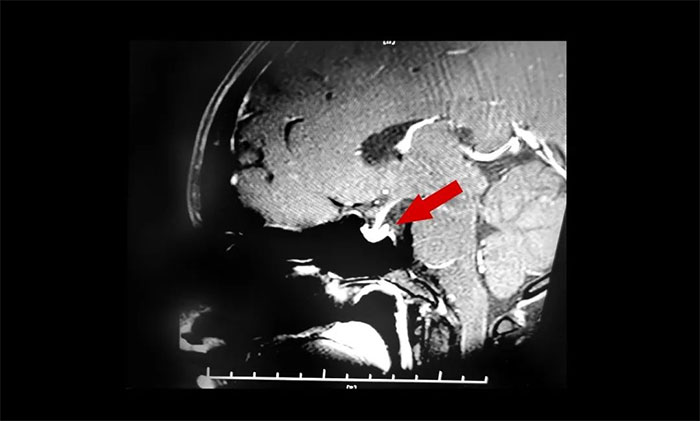

▲ 垂体腺瘤超蝶鞍生长

入院时查体,鞍区MRI平扫+增强显示:蝶鞍稍扩大,鞍底骨质下陷;垂体前叶右侧见一矢横高径约1×1×1cm异常信号灶。检查催乳素超3000μIU/mL,远超正常值。